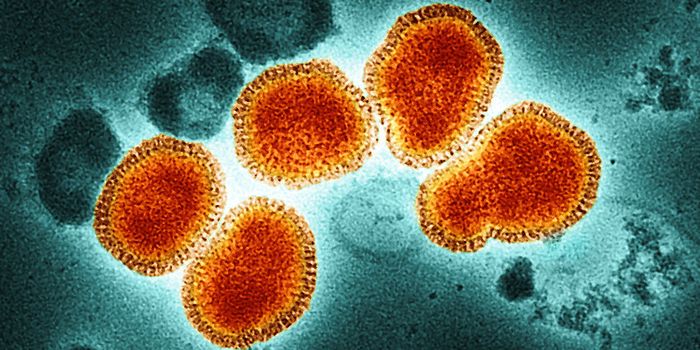

JUL 05, 2022ImmunologyResearchers have created a new 'universal' flu vaccine, which is directed against type A influenza viruses. It w ...

NOV 17, 2021MicrobiologyEvery year, there is a flu outbreak, and the severity can depend on many factors, like what strain is circulating. Last ...

APR 20, 2017Clinical & Molecular DXEven though this year’s peak flu season can be considered to have passed, people can contract the virus well into ...

OCT 17, 2017ImmunologyThe influenza vaccine may not be as effective as it needs to be for young leukemia patients, who are at an especially hi ...